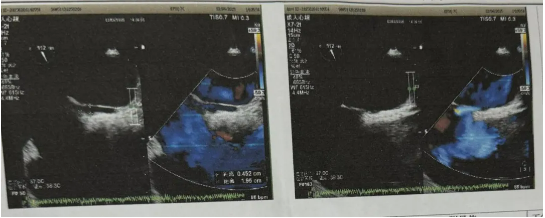

男性患者,35歲,長(zhǎng)期受不明原因偏頭痛困擾,伴頭暈、眼花,發(fā)作起來(lái)疼痛難忍,影響行動(dòng),期間就診神內(nèi)科、耳鼻喉科等,頭顱、頸椎等檢查均無(wú)異常。近日,頭痛癥狀發(fā)作頻繁、藥物緩解效果甚微,為明確病因?qū)で笾委?,患者?lái)我院就診,行經(jīng)顱多普勒檢查,結(jié)果顯示Valsava動(dòng)作后出現(xiàn)大量、高強(qiáng)度栓子信號(hào)(呈雨簾狀),右心聲學(xué)造影結(jié)果也呈陽(yáng)性,支持右向左分流,大量。進(jìn)一步的食道超聲檢查明確診斷:房間隔中段存在一長(zhǎng)約19.5mm、寬約4.5mm的斜形裂隙,確診為卵圓孔未閉(長(zhǎng)隧道型),符合介入封堵指征。

經(jīng)過(guò)術(shù)前精心準(zhǔn)備,手術(shù)順利開(kāi)展,在超聲影像精準(zhǔn)引導(dǎo)下,心胸血管外科團(tuán)隊(duì)通過(guò)股靜脈穿刺建立介入通道,將可降解封堵器精準(zhǔn)釋放在卵圓孔裂隙處。術(shù)中實(shí)時(shí)超聲監(jiān)測(cè)顯示封堵器貼合緊密,分流消失,手術(shù)歷時(shí)僅40分鐘。術(shù)后患者頭痛癥狀顯著緩解,無(wú)需長(zhǎng)期服用抗凝藥物,第二天下床,第三天即出院,生活恢復(fù)正常。(供稿通訊員:凡兵、彭均偉、孫暉)